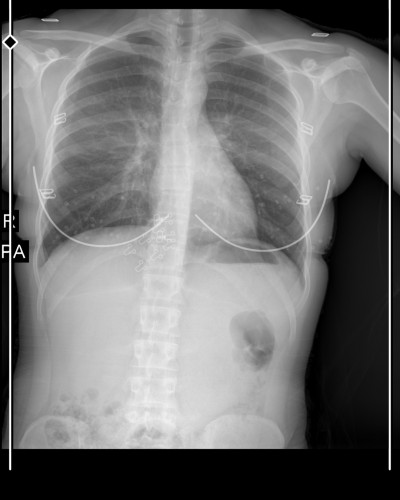

imagekkizlar altaki yuvarlak siyahlık ne bu arada bn astım hastasıyım bunu nasıl atlatabilirim bilginiz varmi

O siyah görünen şey eşimdede vardı sanırım normal doktor birsey yok demisti